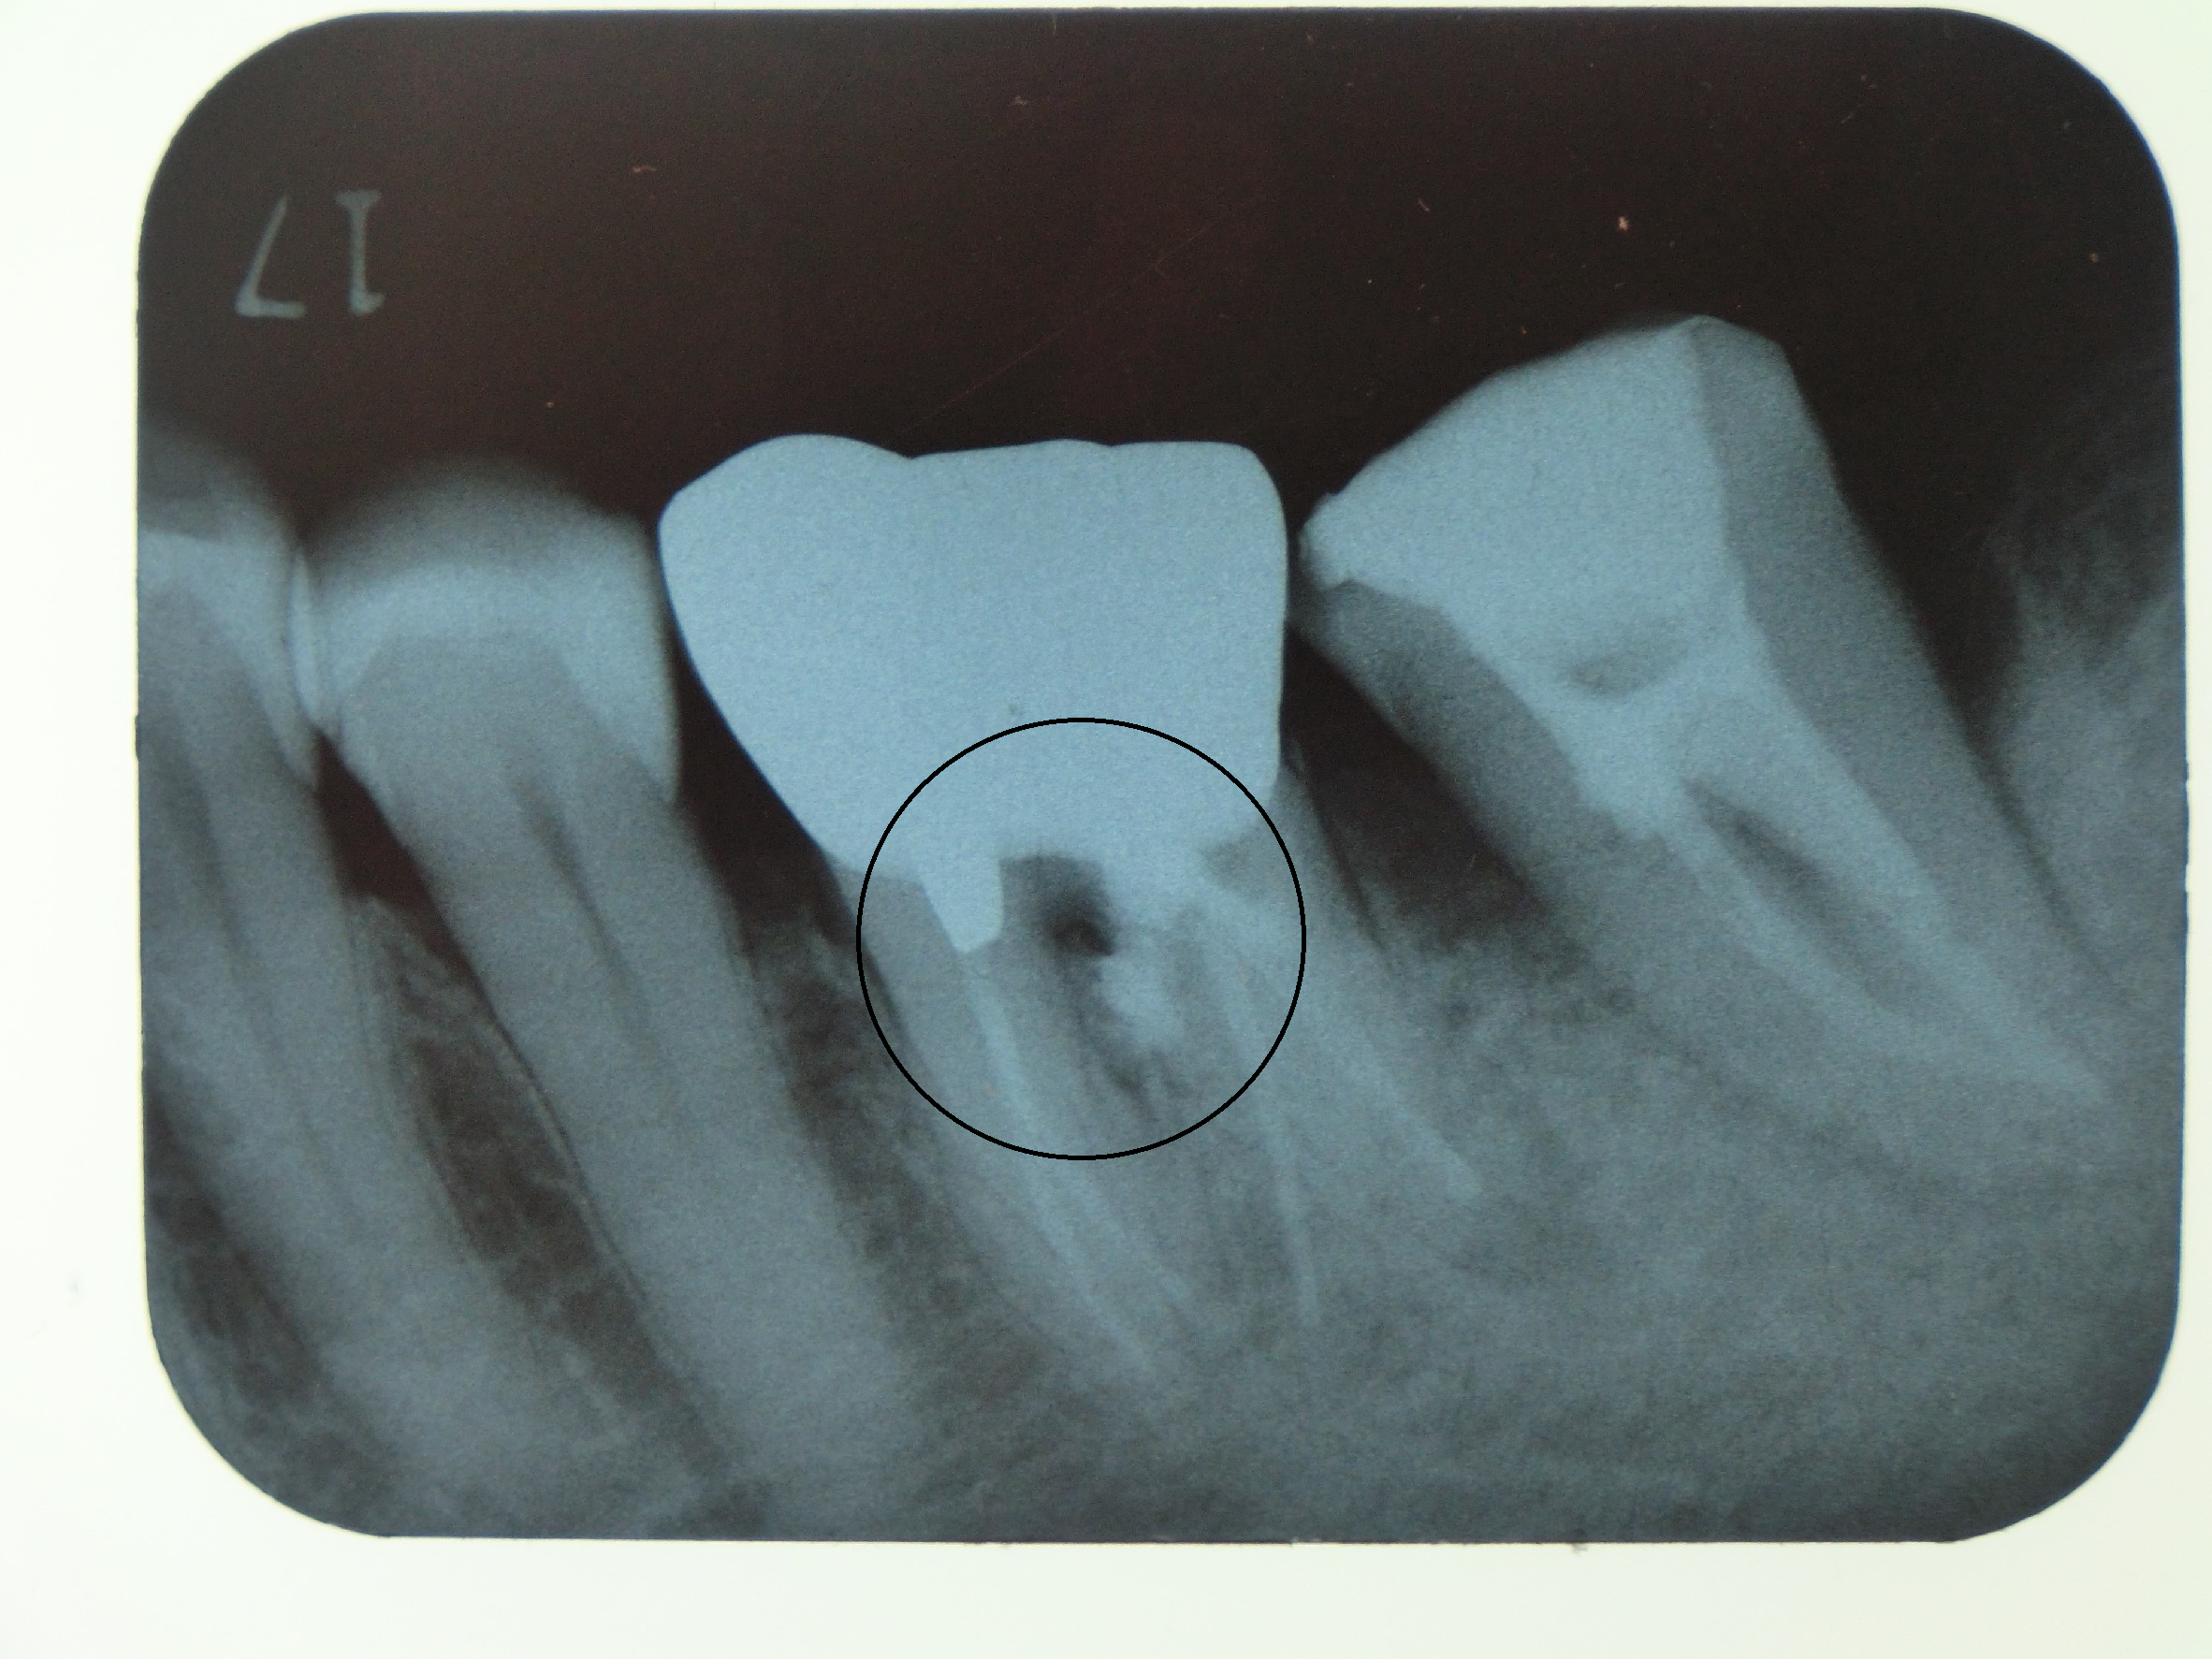

CASE2

5~6年前に虫歯治療で神経を取ったまま放置していたら、急に顎が痛くなり腫れてきたとの事で来院されました。見てみると放置していたことで虫歯が進み、歯の根っこの部分に穴が空いていました。治療方法は、まず感染している虫歯の部分をしっかり除去し、MTAセメントで再感染しないよう穴を封鎖し、その後は通常通りの根管治療をしました。